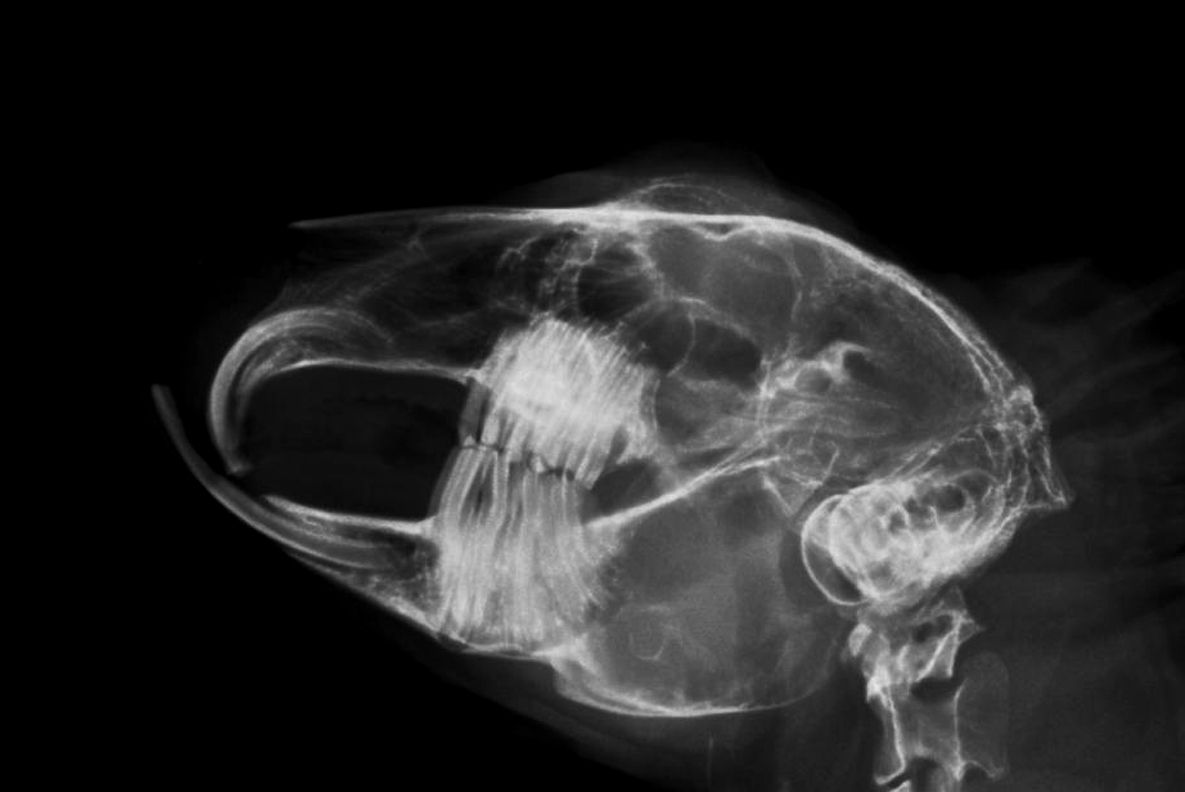

- Zahnheilkunde, Untersuchungen der Maulhöhle in Narkose in Verbindung mit bildgebender Diagnostik (Kopf-/Zahnröntgen), schonende und sichere Zahnkorrekturen mittels elektrisch betriebener Diamantschleifer

- bildgebende Diagnostik (Röntgen, Sonographie, CT-Untersuchungen)